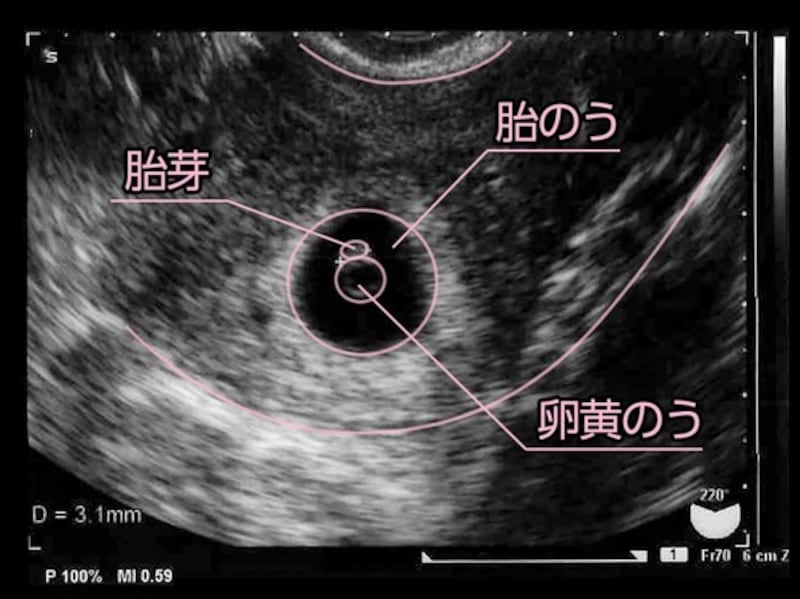

5 産科一般超音波検査 初期編 正常所見4 7週 日本産婦人科医会

妊娠2ヶ月 妊娠4週 5週 6週 7週 妊娠初期 の超音波写真 妊娠 出産 育児に関する総合情報サイト ベビカム

妊娠5週目 胎嚢のエコー写真 つわり症状や流産のこと 妊娠初期 All About

妊娠2ヶ月 妊娠4週 5週 6週 7週 妊娠初期 のおなかの赤ちゃんの様子 妊娠 出産 育児に関する総合情報サイト ベビカム

妊娠5週目 胎嚢のエコー写真 つわり症状や流産のこと 妊娠初期 All About

妊娠2ヶ月 妊娠4週 5週 6週 7週 妊娠初期 の超音波写真 妊娠 出産 育児に関する総合情報サイト ベビカム

妊娠2か月目 妊娠4 7週の胎児の様子 母体の症状や気を付けること 妊娠初期 All About

妊娠2か月目 妊娠4 7週の胎児の様子 母体の症状や気を付けること 妊娠初期 All About

5 産科一般超音波検査 初期編 正常所見4 7週 日本産婦人科医会